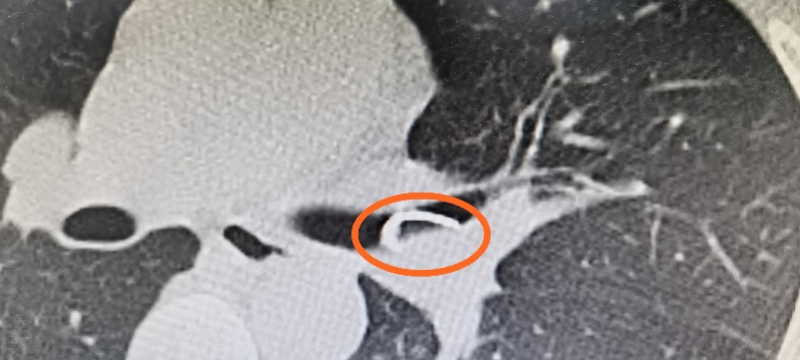

先看影像学检查:胸片,ct,看到了左主支气管内异物以及阻塞性肺不张.

经胸部ct和气道三维重建检查,结果也提示有异物,我们建议做气管